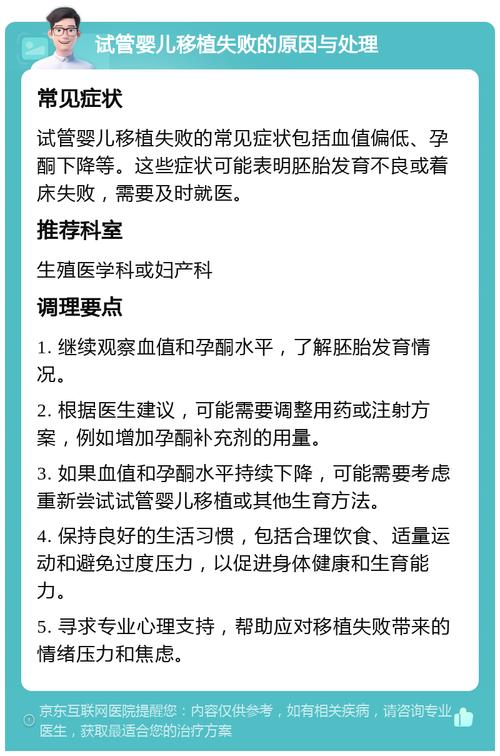

试管婴儿移植失败:原因分析与应对策略

本文围绕试管婴儿移植失败展开,分析了胚胎、子宫、内分泌、免疫等因素导致失败的原因,并结合相关数据说明现状。同时,从心理调适、全面检查等方面给出应对策略,助求子家庭重拾希望。